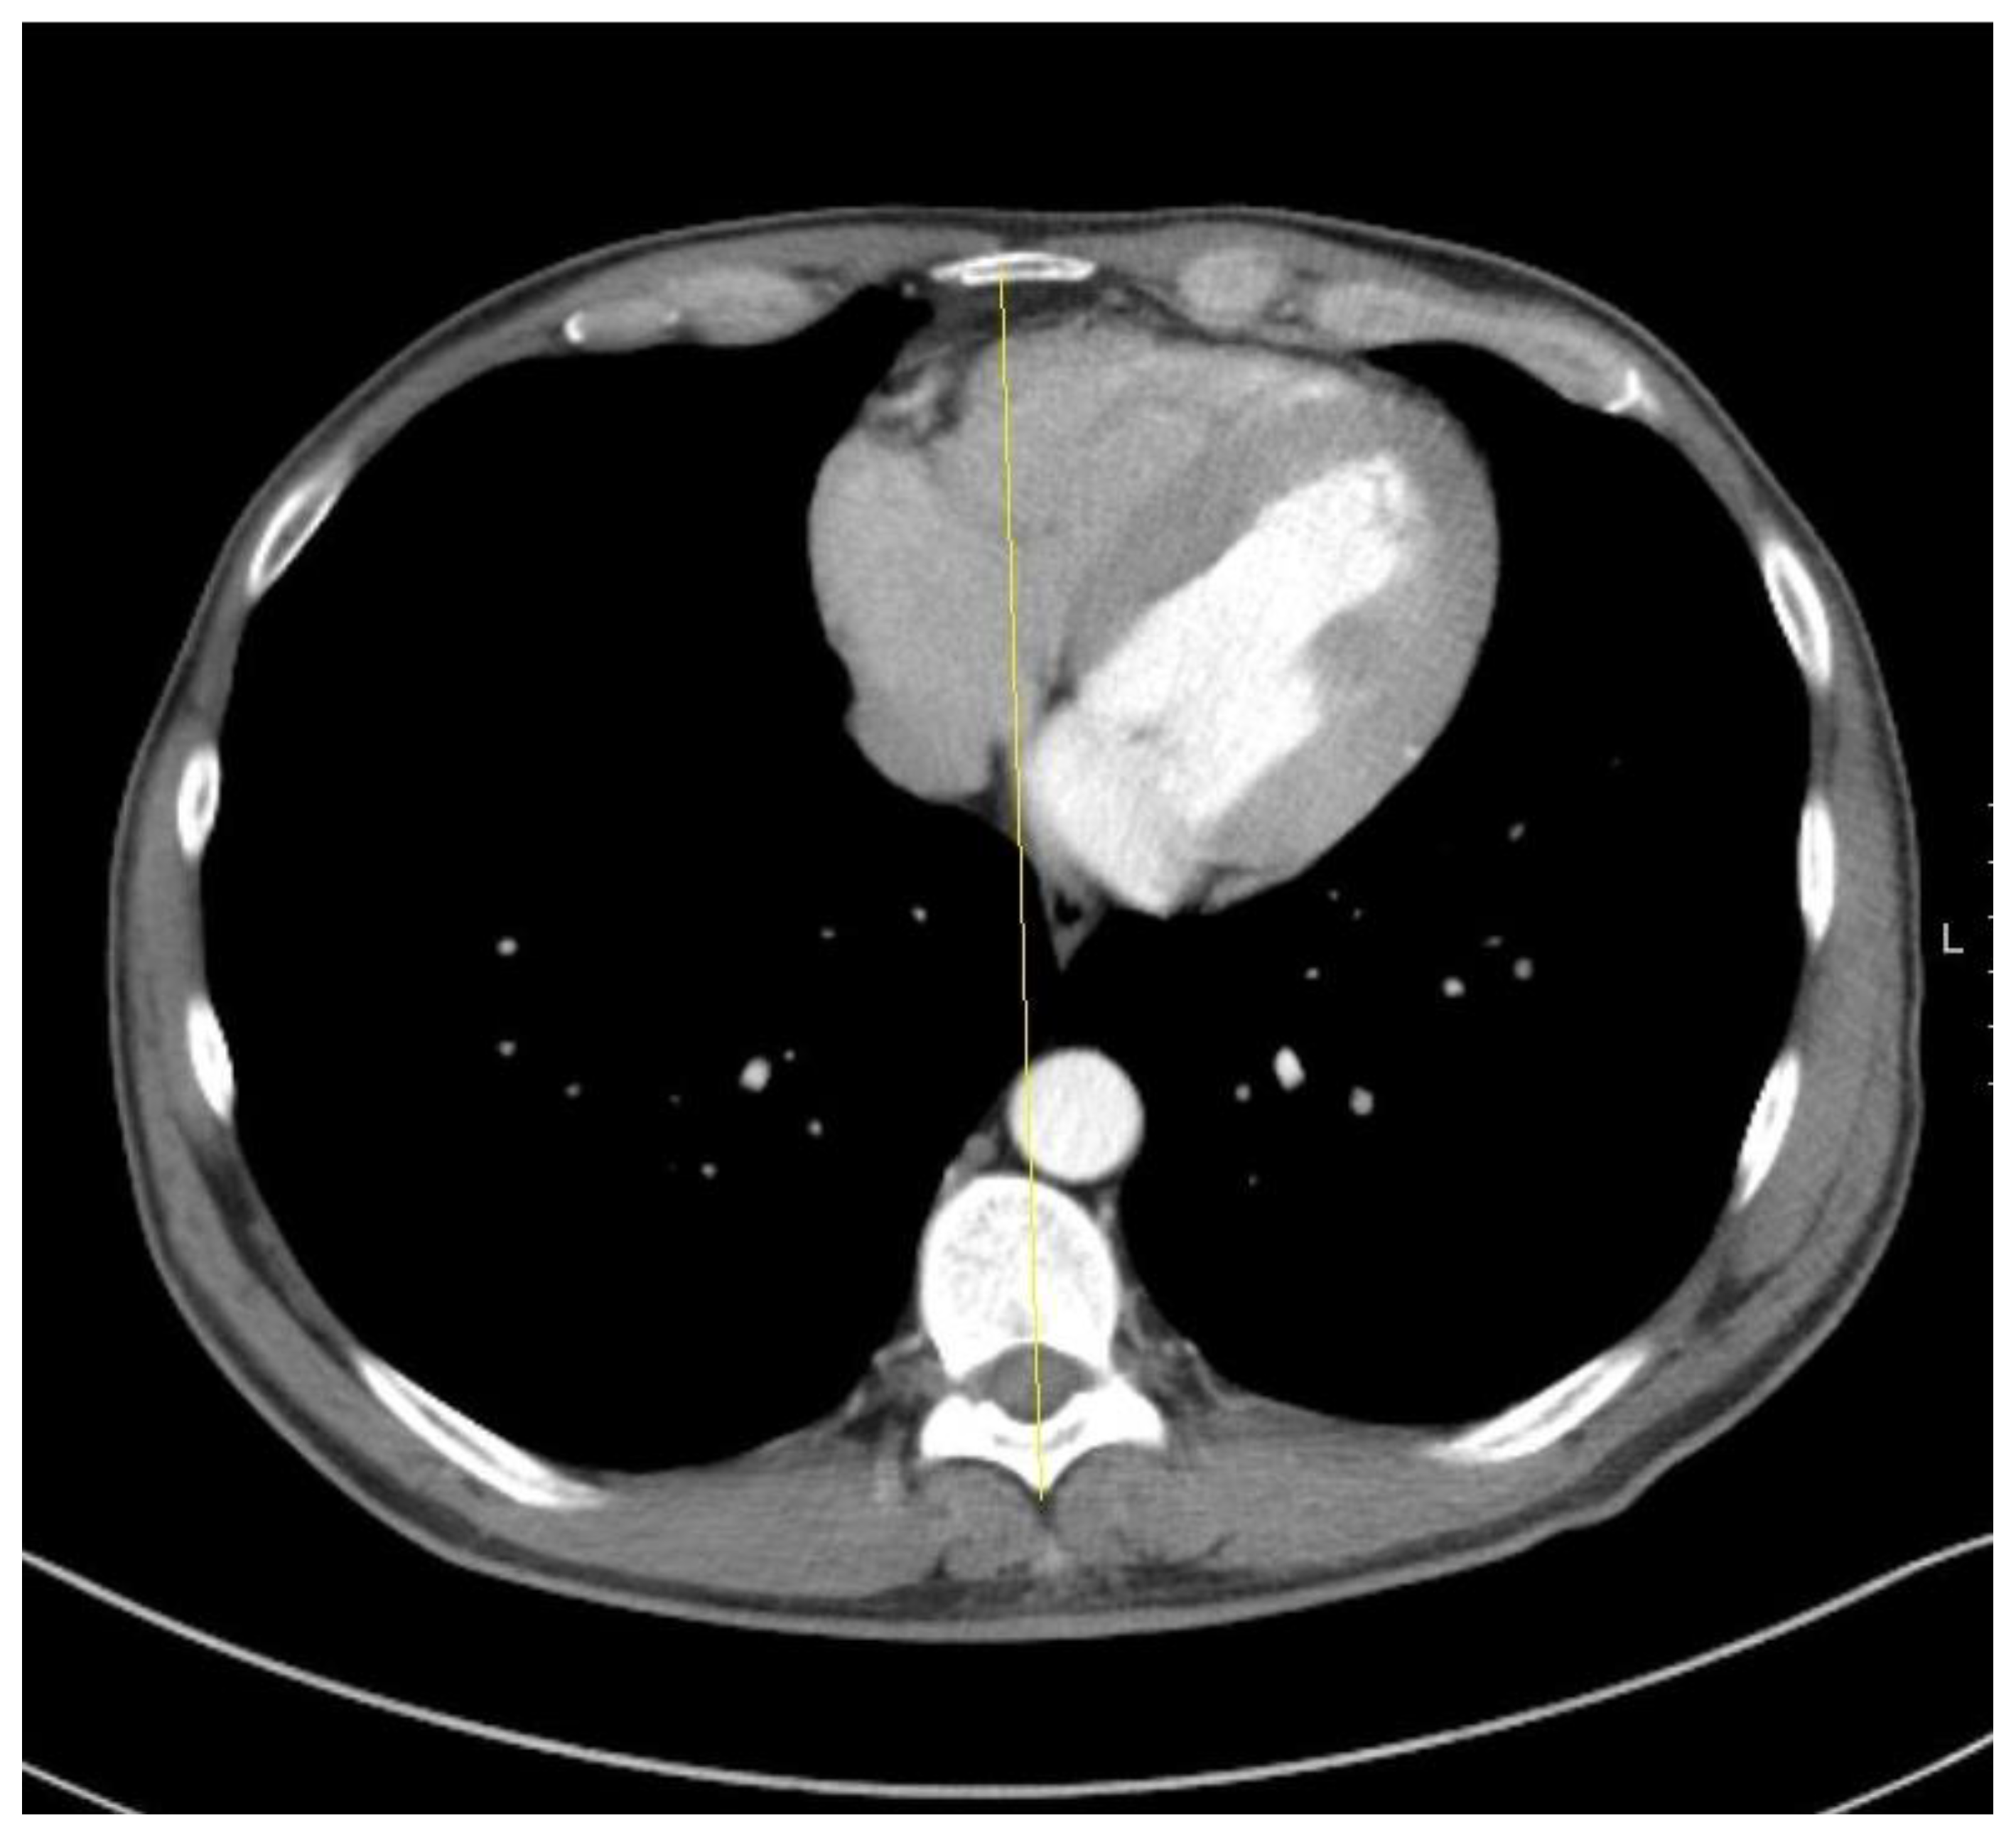

- Larsson, M. Did heart asymmetry play a role in the evolution of human handedness? J. Cult. Cogn. Sci. 2017, 1, 65–76. [Google Scholar] [CrossRef]

- Kang, N.; Hsee, L.; Rizoli, S.; Alison, P. Penetrating cardiac injury: Overcoming the limits set by Nature. Injury 2009, 40, 919–927. [Google Scholar] [CrossRef]

- Muñoz, J.H.M.; Dussan, O.; Ruiz, F.; Rubiano, A.M.; Puyana, J.C. Penetrating cardiac trauma in stab wounds: A study of diagnostic accuracy of the cardiac area. Ulus Travma Acil Cerrahi Derg 2020, 26, 693–698. [Google Scholar] [CrossRef]

- Sandrasagra, F. Management of penetrating stab wounds of the chest: An assessment of the indications for early operation. Thorax 1978, 33, 474–478. [Google Scholar] [CrossRef]